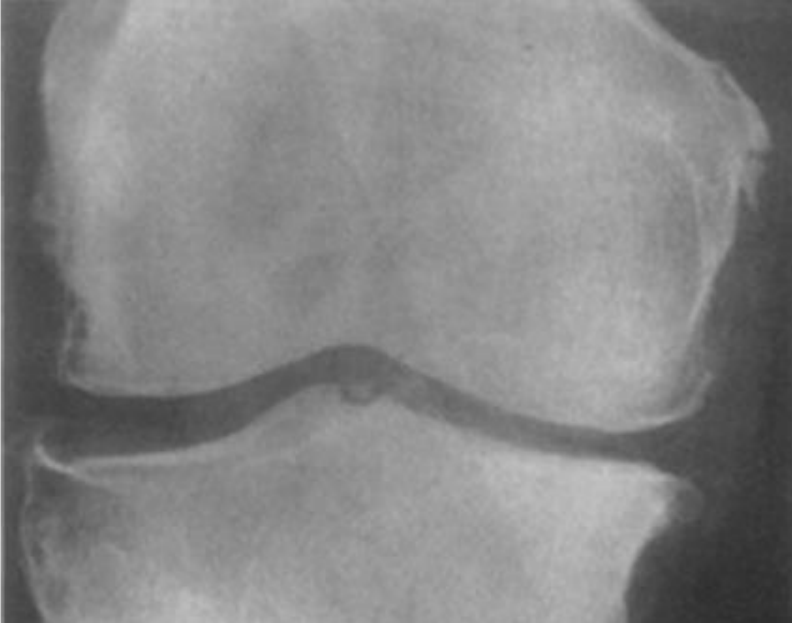

Visto a importância da classificação de osteoartrose de joelho, visando seu prognóstico, a classificação de Kellgren-Lawrence é muito utilizada, na imagem abaixo, qual a adequada classificação da mesma: